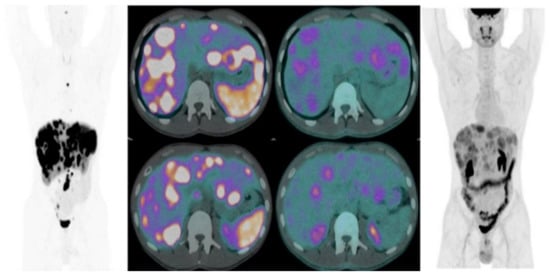

- Chan, D.L.; Pavlakis, N.; Schembri, G.P.; Bernard, E.J.; Hsiao, E.; Hayes, A.; Bailey, D.L.; Pavlakis, N.; Schembri, G.P. Dual somatostatin receptor/FDG PET/CT imaging in metastatic neuroendocrine tumours: Proposal for a novel grading scheme with prognostic significance. Theranostics 2017, 7, 1149. [Google Scholar] [CrossRef] [PubMed]